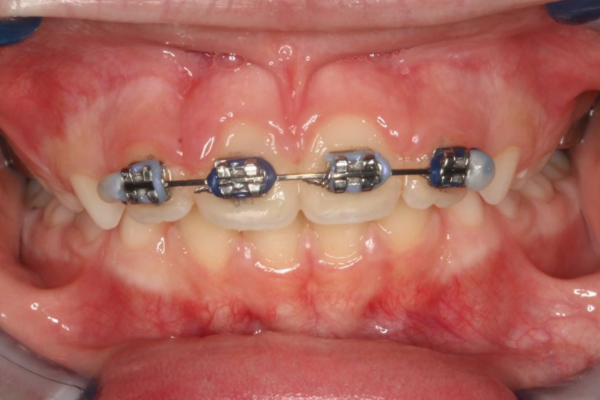

Cada paciente y cada tratamiento es único. El profundo conocimiento de la anatomía y de nuestros pacientes junto con la tecnología más avanzada nos permite realizar diagnósticos certeros. Localizando el origen del problema muchas veces incluso antes de que se produzca evitando así su aparición.

"Guiando el crecimiento facial de tu hijo"

con ortopedia y ortodoncia, paso a paso.